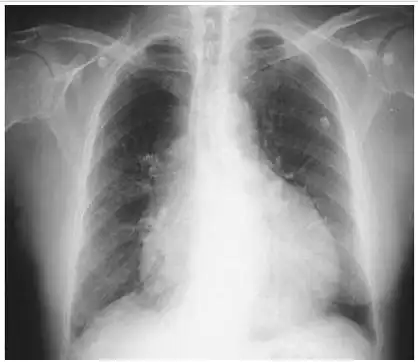

烧瓶心我的妈呀第一次见这么标准的